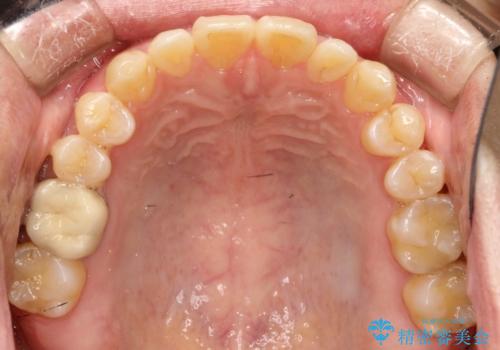

前歯の隙間 インビザラインにて整った歯並びへ

- 前歯の隙間が気になるとのことで来院されました。

インビザラインにて矯正治療を行うこととしました。

下の歯と歯の間にわずかに隙間をつくり、上の前歯の隙間を閉じました。